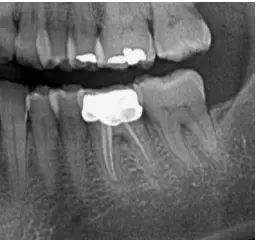

Røntgenbillede af tand med rodbehandling hos Tandlægerne Ølandshus

1. Diagnose: Før behandlingen starter, foretager tandlægen en grundig undersøgelse og tager røntgenbilleder for at vurdere omfanget af skaden og for at vurdere nerven og rodkanalernes anatomi. Herudfra planlægges behandlingsforløbet.